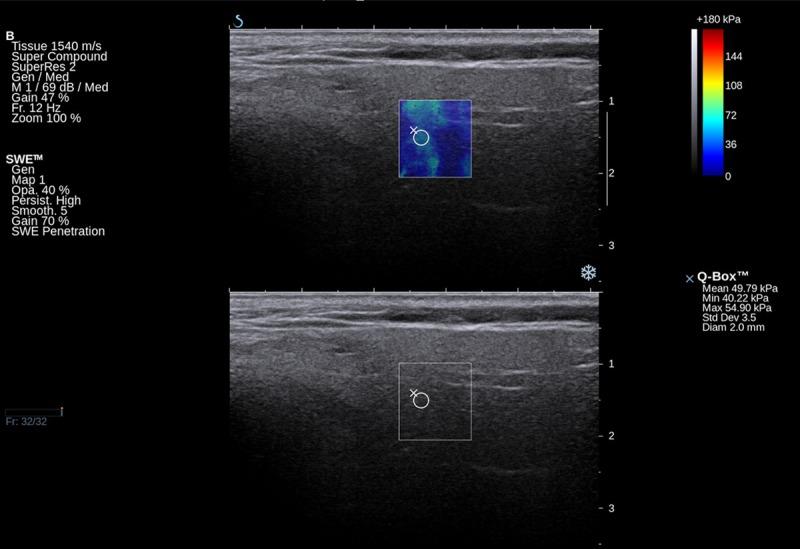

Shear wave elastography (SWE) is widely used in breast, liver, prostate and thyroid evaluations. Elastography provides additional information if used to assess parotid gland pathology. We assessed parotid glands by means of SWE to compare the parenchyma properties in different types of inflammation.

MATERIAL/METHODS: Prospective analysis included 78 consecutive patients with parotid gland pathology: sialolithiasis (33), Stensen's duct stenosis (15), chronic inflammation (10), and primary Sjögren syndrome (pSS) (20) treated at the Department of Otolaryngology, Head and Neck Surgery of PUMS. The primary predictor variable was type of parotid pathology, and secondary predictor variables were patient age and the duration and intensity of complaints. Ultrasound pictures were compared with elastography values of parotid parenchyma.

Mean elasticity values for pSS (111 Kilopascals (kPa), Stensen's duct stenosis (63 kPa), sialolithiasis (82 kPa), and chronic inflammation (77 kPa) were significantly higher than the mean value for healthy patients (24 kPa). Elasticity increased proportionally to the intensity of complaints: mild (51 kPa), moderate (78 kPa), and strong (90 kPa). Increased elasticity did not correspond with ultrasonographic pictures. In pSS the parenchyma was almost twice as stiff as in chronic inflammation (p=0.02), although subjective complaints were mostly mild or moderate, and the ultrasonographic picture did not present features of fibrosis.

剪切波弹性成像(SWE)广泛应用于乳腺、肝脏、前列腺和甲状腺的评估。如果用于评估腮腺病变,弹性成像可提供额外信息。我们通过SWE评估腮腺,以比较不同类型炎症中的实质特性。

材料/方法:前瞻性分析纳入了78例连续的腮腺病变患者,这些患者在PUMS头颈外科耳鼻喉科接受治疗,其中包括涎石病(33例)、腮腺导管狭窄(15例)、慢性炎症(10例)和原发性干燥综合征(pSS)(20例)。主要预测变量是腮腺病变类型,次要预测变量是患者年龄、症状持续时间和强度。将超声图像与腮腺实质的弹性成像值进行比较。

pSS的平均弹性值(111千帕斯卡(kPa))、腮腺导管狭窄(63 kPa))、涎石病(82 kPa))和慢性炎症(77 kPa))显著高于健康患者的平均值(24 kPa)。弹性与症状强度成比例增加:轻度(51 kPa)、中度(78 kPa)和重度(90 kPa)。弹性增加与超声图像不相符。在pSS中,实质硬度几乎是慢性炎症的两倍(p = 0.02),尽管主观症状大多为轻度或中度,且超声图像未显示纤维化特征。